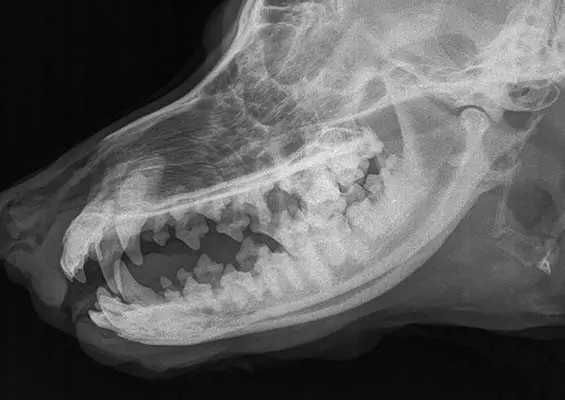

Kamienie ślinowe u psów – opis przypadku